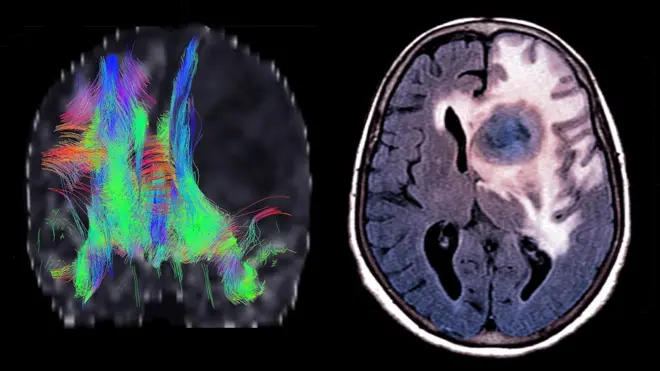

Garaacha akkamiin murtee baasta?

Dhaabbati Qorannoo Kaansarii UK akka jedhutti qaccee sanyii kaansariidhaan faalameef yaaliin taasifamu jira.

Dhiiga qorachuu fi raajii kaasuun hojii duraati

Wal'aansi garaacha muranii baasuu kun 'gastrectomy' jedhama.

Wayita garaachu bakki rakkoo qabu muramu toorri nyaatni keessa taru garaacha isa hafetti qabsiifama.

Kana jechuun qaamni nama kanaa ammallee sirna nyaataa ni raawwata jechuudha. Akka duraanii garuu hin ta'u.